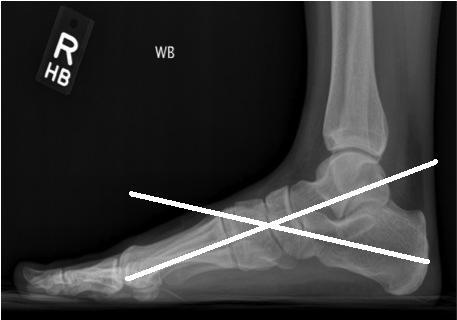

using the lateral view of the foot, angle formed between the longitudinal axes of the talus ( RID2949) and calcaneus ( RID2959 )

if < 35 degrees then varus deformity ( RID4769 ); clubfoot, cavus foot

if > 50 degrees then valgus deformity ( RID4768 ); congenital vertical talus, skewfoot deformities, flatfoot

how to draw the lateral talocalcaneal angle